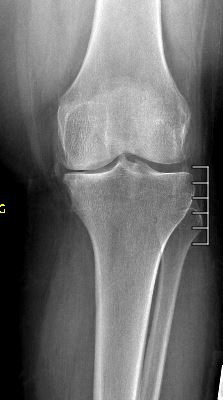

Example X-Ray Images

Medial Compartment Arthritis